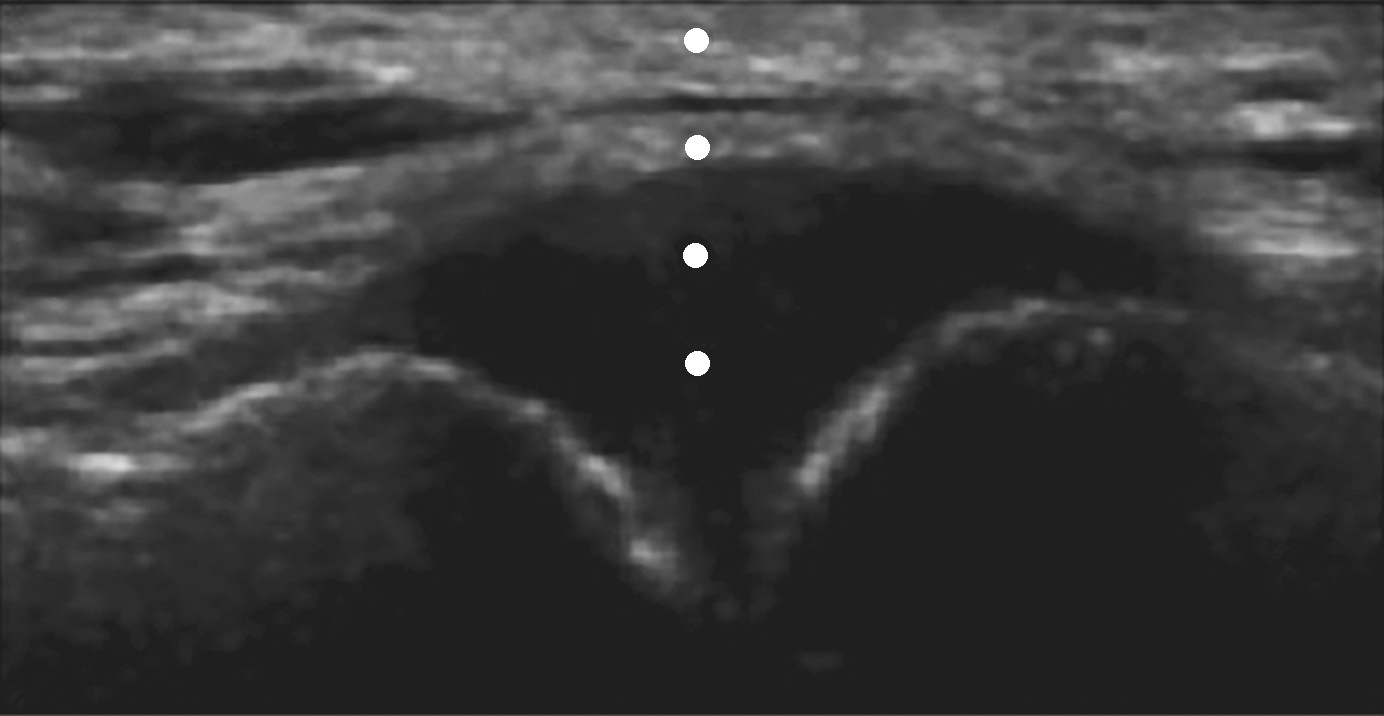

▲ 图2-4-3 超声引导下肩锁关节腔介入治疗超声图(二)

平面外进针法,圆点:进针过程中针尖出现的位置